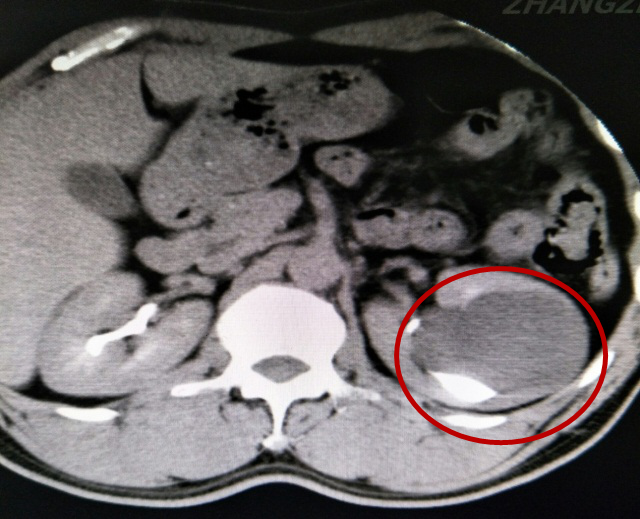

46岁的林先生最近比较烦恼,左侧肾脏长了个囊肿直径达8cm,医生告诉他如果不做手术,就有可能因剧烈活动或腰部外伤导致肾囊肿破裂,引发出血可危及生命。

经过慎重考虑,林先生求诊于漳州市中医院泌尿外科,接诊医生为陈惠新副主任医师。林先生的囊肿长在了肾盂的旁边,术语叫肾盂旁囊肿,周围被肾脏的实质严密包围着,稍有不慎就会损伤大血管引起大出血,危及生命。

为了确保手术顺利实施,泌尿外科全体医师对手术方式、术中可能出现的问题及应对措施进行认真地讨论,经多方论证决定采用特殊体位“斜仰截石位”,在B超引导下穿刺精确定位,实施输尿管软镜下肾盂内激光切开盂旁囊肿内引流术。